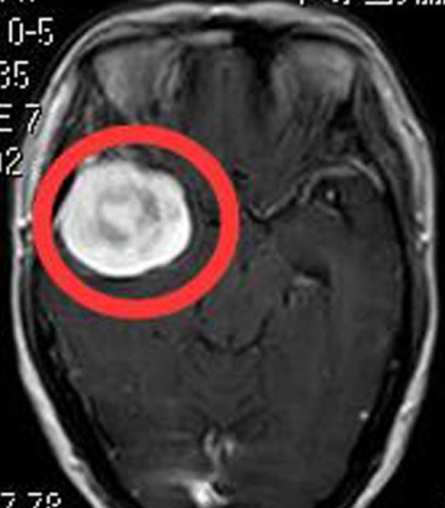

48岁的赵先生,因为突发癫痫就医,家人带其MRI检查后发现大脑左额镰旁有肿瘤占位,病理结果是 脑膜瘤 。 两次手术治疗后依然恶化 由于赵先生才48岁,...

头痛是生活中常见的症状,大多人都出现过头痛、头晕症状,但一般吃点药或过一段时间就好了。而51岁的李女士(化名),却近来因为莫名头痛,在医院核磁...

提及肿瘤,想必大家都不陌生,在许多人眼中是不治之症,也没有人会喜欢它。但是你承认的,有时候它确实离我们很远,但有时候,却离我们很近。 常年...